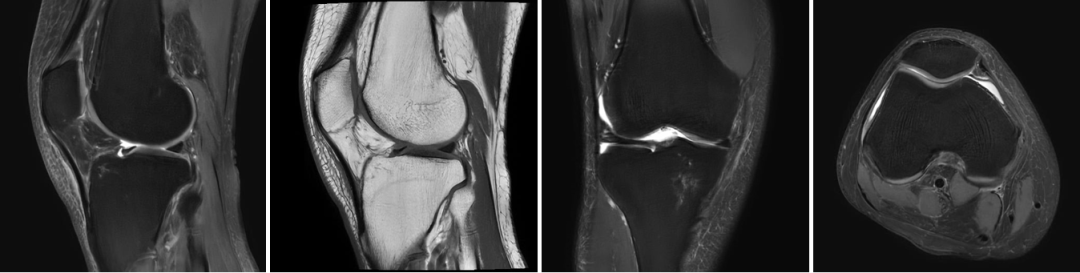

骨关节:膝关节半月板/韧带损伤、肩袖撕裂、股骨头坏死等;

膝关节

肩关节

3.0T高场强带来的极致成像效果,能清晰显示神经系统、体部脏器、骨关节、心血管等部位的细微病变,无论是早期脑梗塞、微小脑肿瘤,还是肝癌、胰腺癌等恶性肿瘤的早期筛查,亦或是肩袖撕裂、半月板损伤等软组织损伤,都能精准捕捉,让病灶无处隐藏。